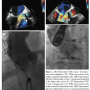

He was deemed to be a high-risk candidate for any surgical intervention due to his critical state (logistic EuroSCORE of 56%, EuroSCORE II of 41.1%), re-do sternotomy, and extensive chest wall collaterals from prior coarctation. After careful review by a multidisciplinary team, the patient was considered for valve-in-valve TAVR. He underwent expedited TAVR evaluation with peripheral and coronary angiography immediately prior to valve replacement. Using transesophageal echocardiogram (TEE; Figure 1A) and aortic root angiography, a 26 mm Edwards Sapien was chosen and successfully deployed via transfemoral approach. The pulmonary artery systolic pressure (PAPs) dropped from 75 to 40 mm Hg following intervention. The procedure was complicated by high-grade atrioventricular block requiring permanent pacemaker placement. Follow-up imaging demonstrated no significant residual transvalvular or perivalvular AI (Figure 1B). He was discharged 14 days after the procedure. At 4-month follow-up exam, the patient’s condition was much improved, with minimal heart failure symptoms and restored renal and liver function.

s/p bioprosthetic aortic valve replacement and 5-vessel coronary artery bypass in 1999 presented to an outside hospital with acute onset of chest pain and shortness of breath. He was diagnosed with an acute non-ST elevation myocardial infarction. Coronary angiogram demonstrated patent bypass graft and severe aortic regurgitation due to degenerative and failing bioprosthesis. This was confirmed by TEE (Figure 1C). The initial ejection fraction was estimated to be 45%.

Due to his comorbidities, re-do sternotomy, and frailty, he was considered to have prohibitive risk for surgical aortic valve replacement (logistic EuroSCORE of 82.1%, EuroSCORE II of 52.6%) and was transferred to our institution to be considered for TAVR. Within 12 hours from transfer, the patient’s condition quickly deteriorated with refractory hypotension, high-grade atrioventricular block, and asystole. The patient received 20 minutes of cardiopulmonary resuscitation and emergent temporary transvenous pacemaker. Due to his tenuous status and high surgical risk, he was considered for compassion use of TAVR. He also had expedited TAVR evaluation with peripheral angiography immediately prior to procedure. He underwent successful TAVR with a 23 mm Sapien valve via transfemoral approach. Intraoperative TEE demonstrated no valvular AI and trace paravalvular leak. The PAPs dropped from 76 to 34 mm Hg following intervention. Due to persistent high-grade atrioventricular block, a permanent pacemaker was placed. There was resolution of heart failure symptoms (Figure 1D) and the patient was discharged from the hospital 5 days after the procedure.